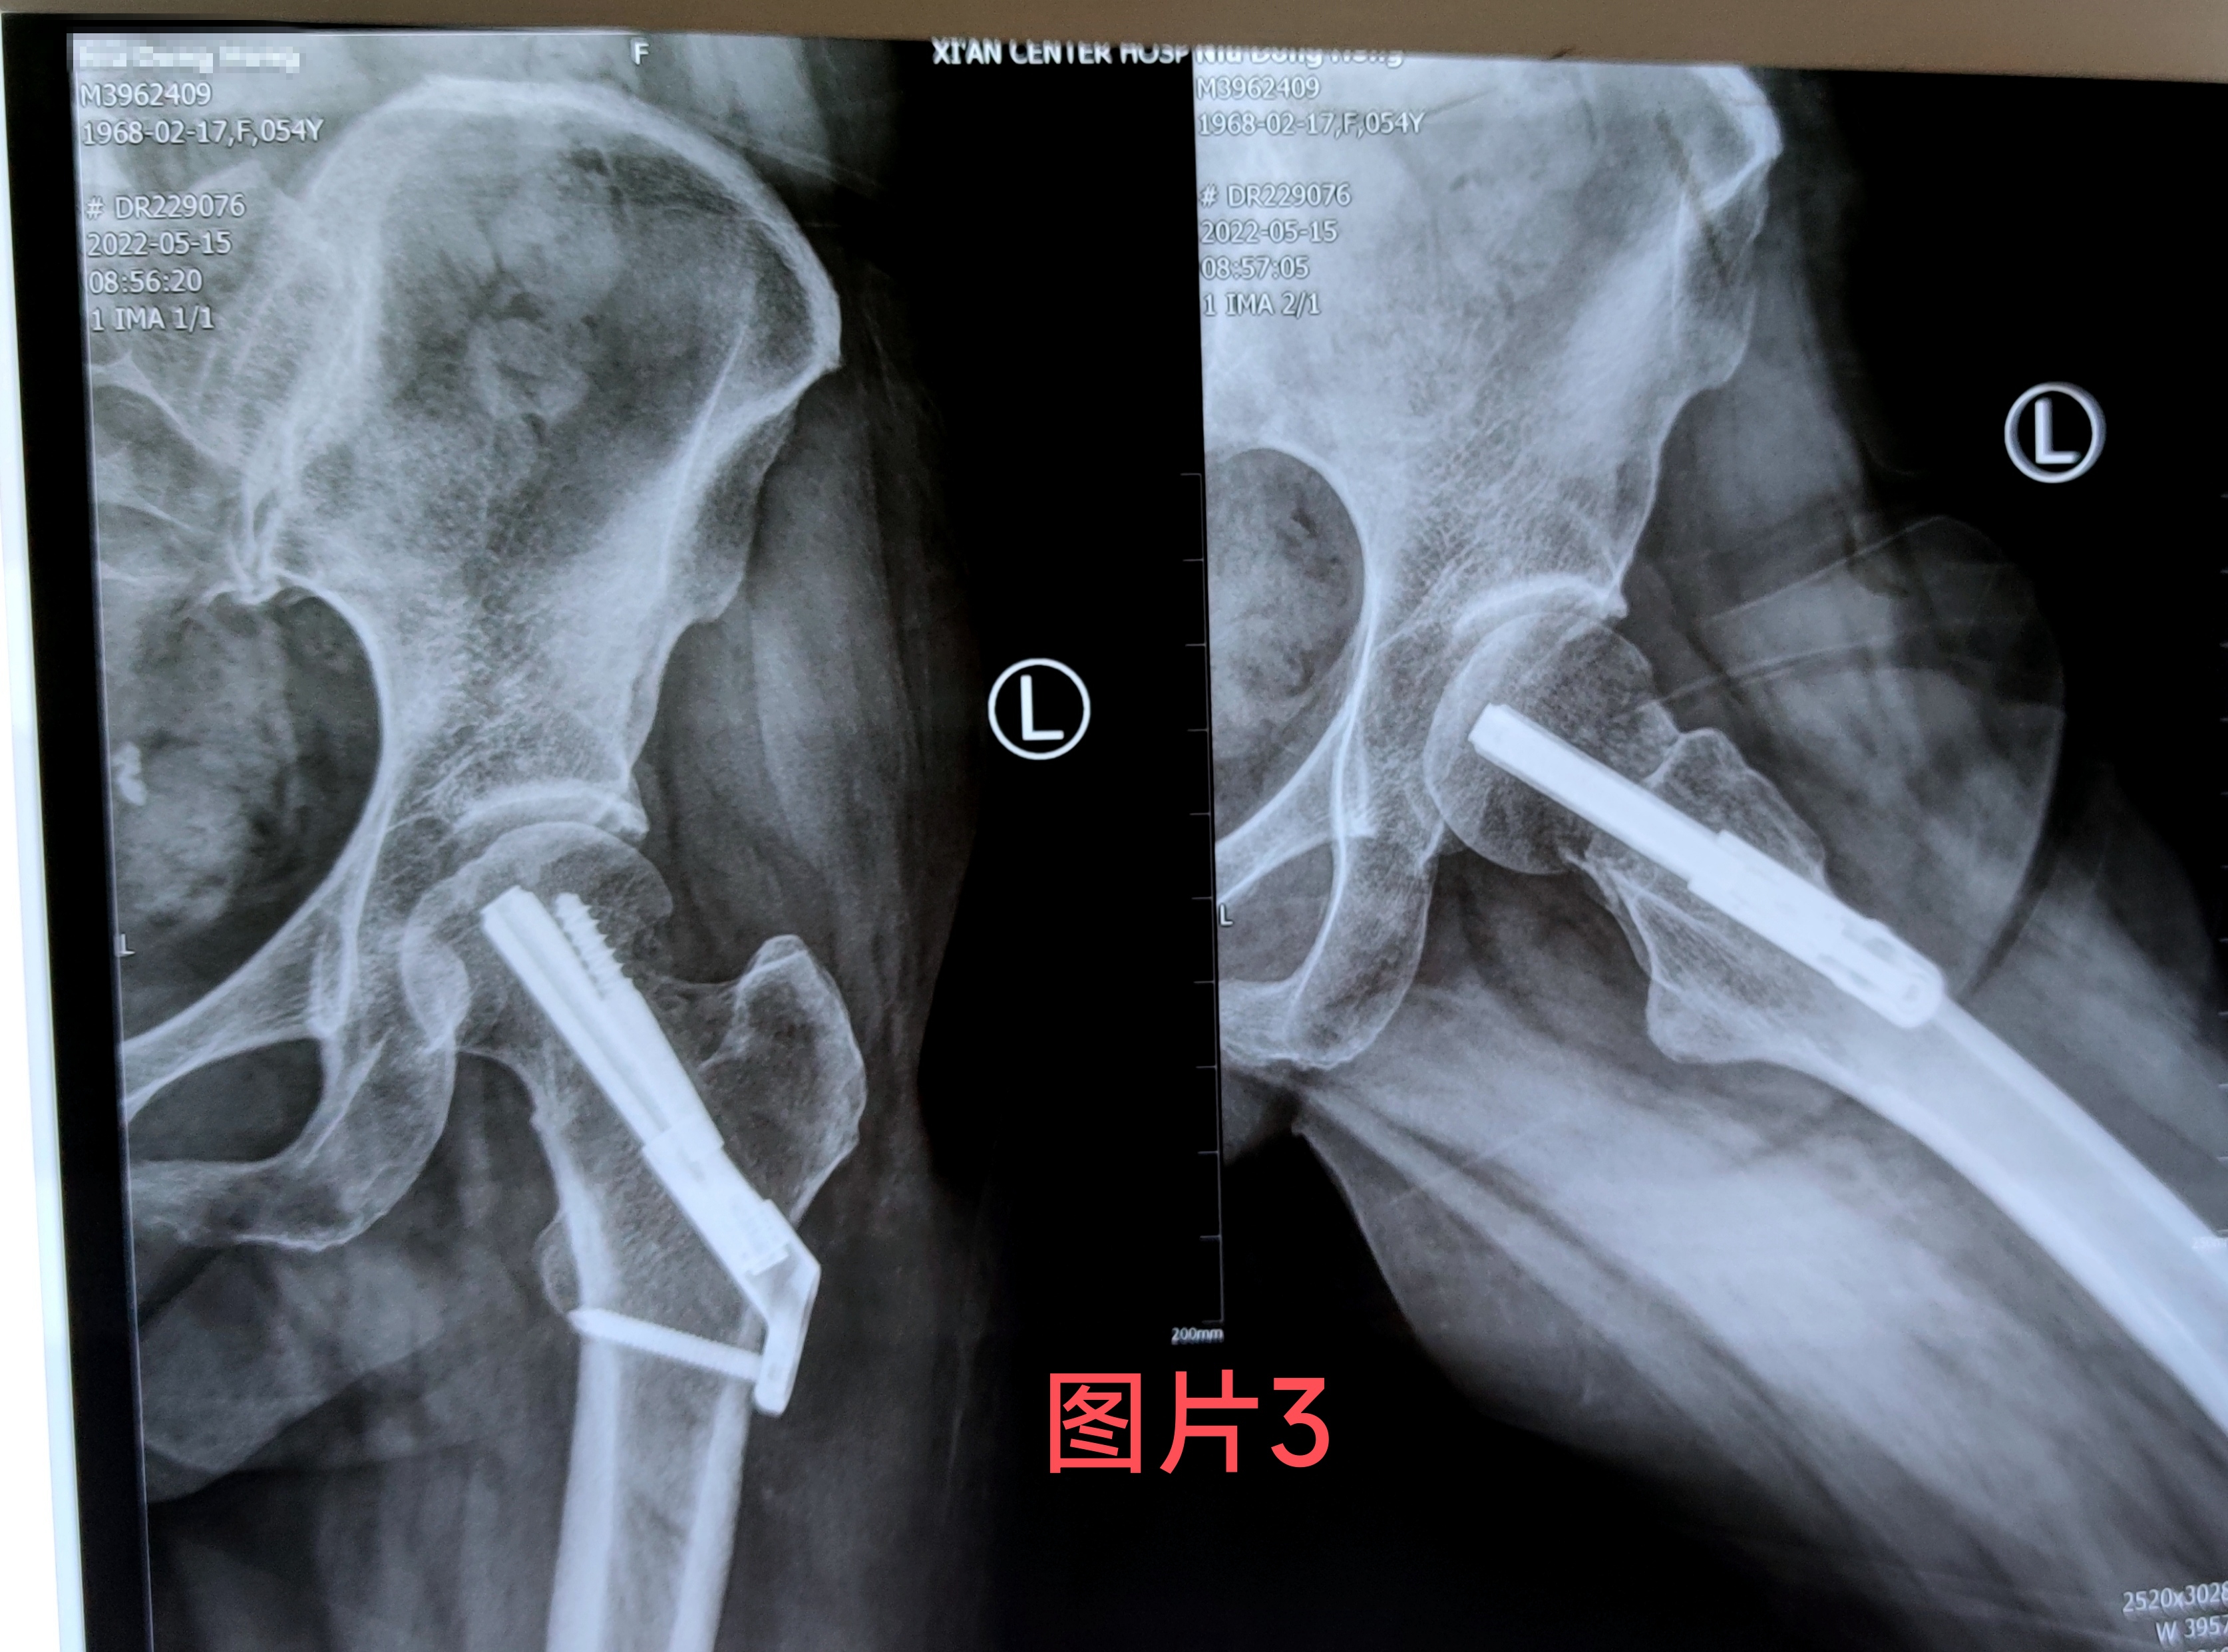

在做好相关术前准备后王涛主任医生为患者行骨折闭合复位FNS内固定手术,手术仅用半小时,手术切口3公分,手术创伤及时间比传统内固定手术大大减少,手术过程不对骨折周围血供产生干扰,最大可能地降低股骨头坏死的几率,术后当天患者无诉疼痛不适,随即开始功能锻炼。(图2)经一月复查固定牢靠,骨折无移位,无不适感(图3)。据王涛主任医生介绍股骨颈内固定系统(FNS)具有微创手术。时间短,创伤小,内固定支撑能力,防旋能力更为突出。具有力学稳定,滑动加压等优点,有利于患者早期恢复,降低股骨颈骨折不愈合发生率。王涛主任医生带领张磊卢洋主治医生治疗团队目前已为3例进行了此类手术均取得良好的手术疗效及治疗经验。填补了色花堂 空白。